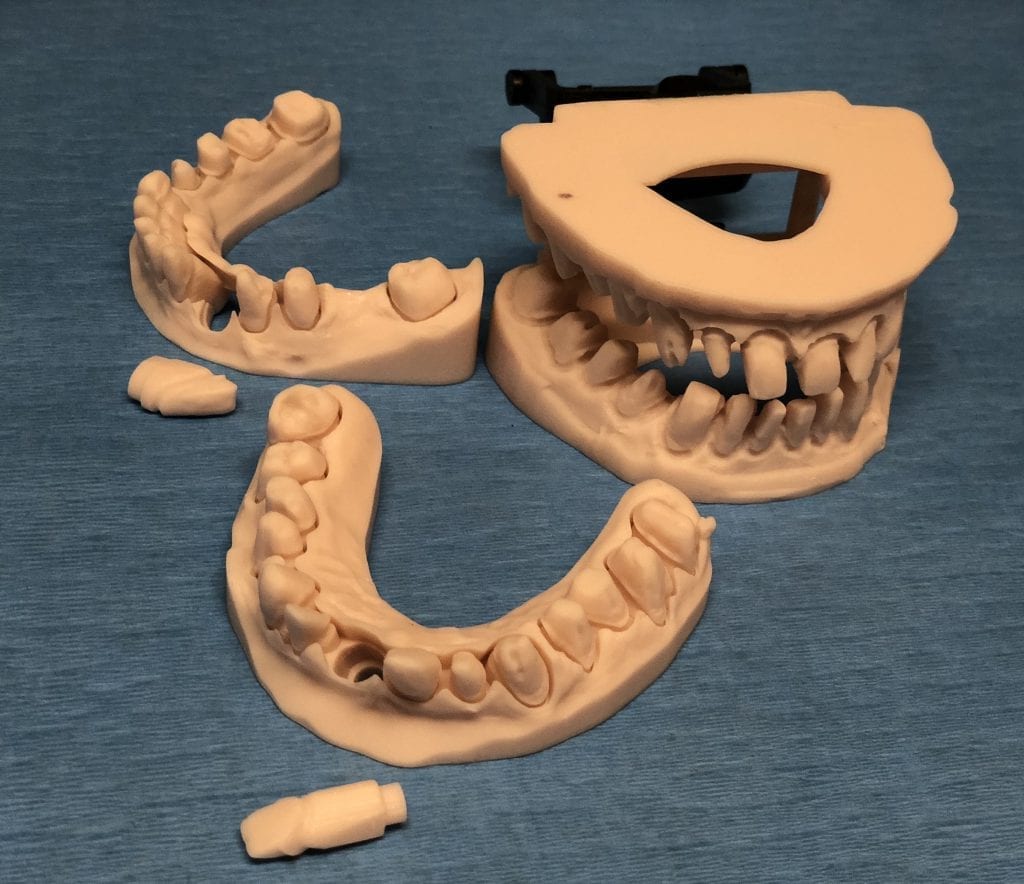

The case was designed by CADENT BESSA, and the models were printed by Burbank Dental Lab with Carbon Printers. There restorations were milled and cut back and layered by Burbank Dental Lab

IMAGES OF PRINTED MODELS